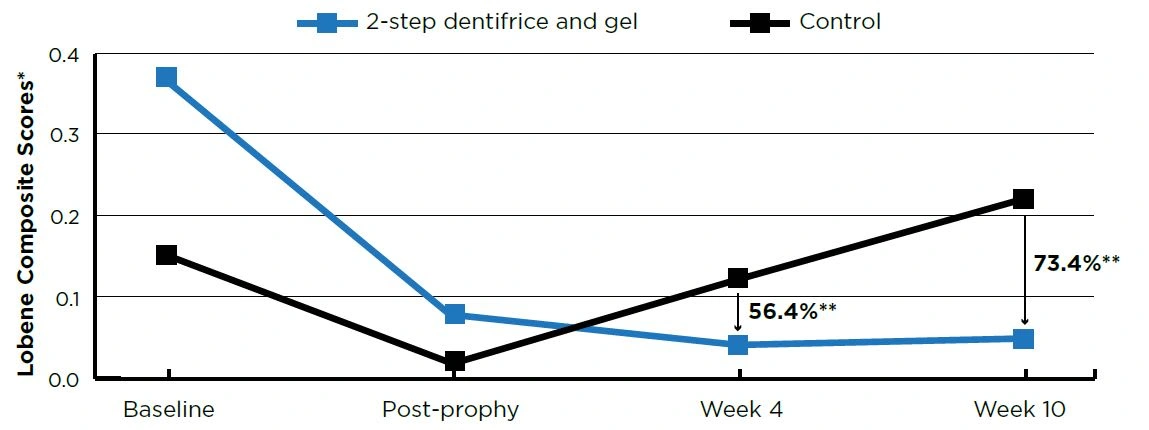

A 2-step dentifrice and whitening gel system helped maintain the cleaning results of a dental prophylaxis versus a regular anti-cavity dentifrice used as a negative control through 2.5 months. Step 1 is a 0.454% stannous fluoride dentifrice and Step 2 is a 3% hydrogen peroxide whitening gel.

After 10 weeks of twice daily use, the 2-step dentifrice and gel system exhibited statistically lower (P<0.001) percent accumulations versus the control group in tooth stain (73.4%), plaque (30.5%), and calculus (58.6%). See Figures 1–3.

Figure 1. Tooth Stain Scores

Figure 1. Tooth Stain Scores

- Baseline and post-prophy scores are means; Week 4 and Week 10 scores are adjusted means ** P<0.0005

To assess the effectiveness of a daily 2-step dentifrice and gel system to prevent the formation of stain, calculus and plaque after a dental prophylaxis.

METHODS

This was a randomized, controlled, examiner-blind, 2-treatment parallel group study. Forty-eight healthy adult volunteers with evidence of plaque and either stain or calculus completed the trial.

Following a whole-mouth dental prophylaxis, subjects were randomized to one of two groups:

- Negative control - 0.76% sodium monofluorophosphate dentifrice (Colgate® Cavity Protection, Colgate-Palmolive)

- Daily 2-step dentifrice and gel system (Crest® PRO-HEALTH™ [HD]™) - Step 1, 0.454% stannous fluoride dentifrice; Step 2, 3% hydrogen peroxide whitening gel

Both groups brushed twice daily with a soft manual toothbrush (Oral-B® Indicator™, Procter & Gamble).

Stain (Lobene Index1), calculus (Volpe-Manhold Index2) and plaque (Rustogi Modification of the Navy Plaque Index3) were measured clinically prior to receiving a dental prophylaxis, immediately after a dental prophylaxis, and after 4 and 10 weeks of product use.